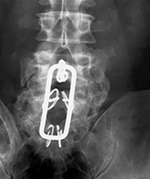

Harms vertebral cage (AP view) |

Harms vertebral cage (lateral view) |

There is a vertebral cage and side plate and screws in the lower thoracic spine for treatment of a spinal tumor. |